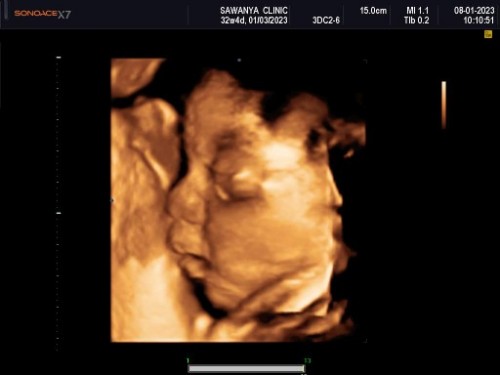

แม่ๆคนไหน ซาวด์ 4 มิติบ้างคะ

น้องไม่ให้ดูหน้าชัดๆเลย 🥰

บ้านนี้น้องให้ดูเเต่ข้างๆค่ะ🥰